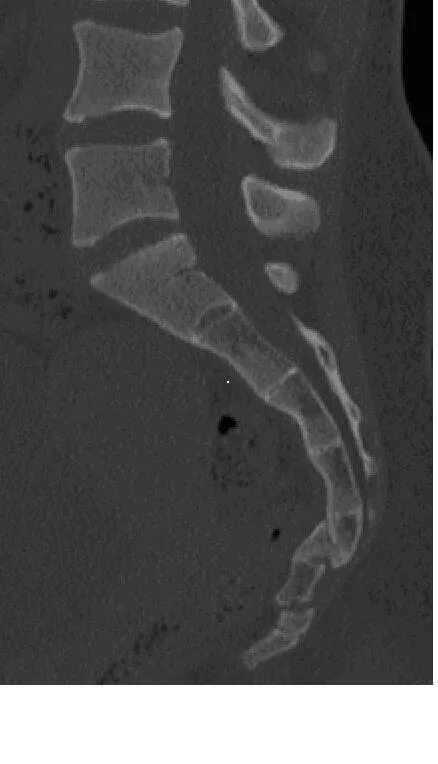

Смещение копчика